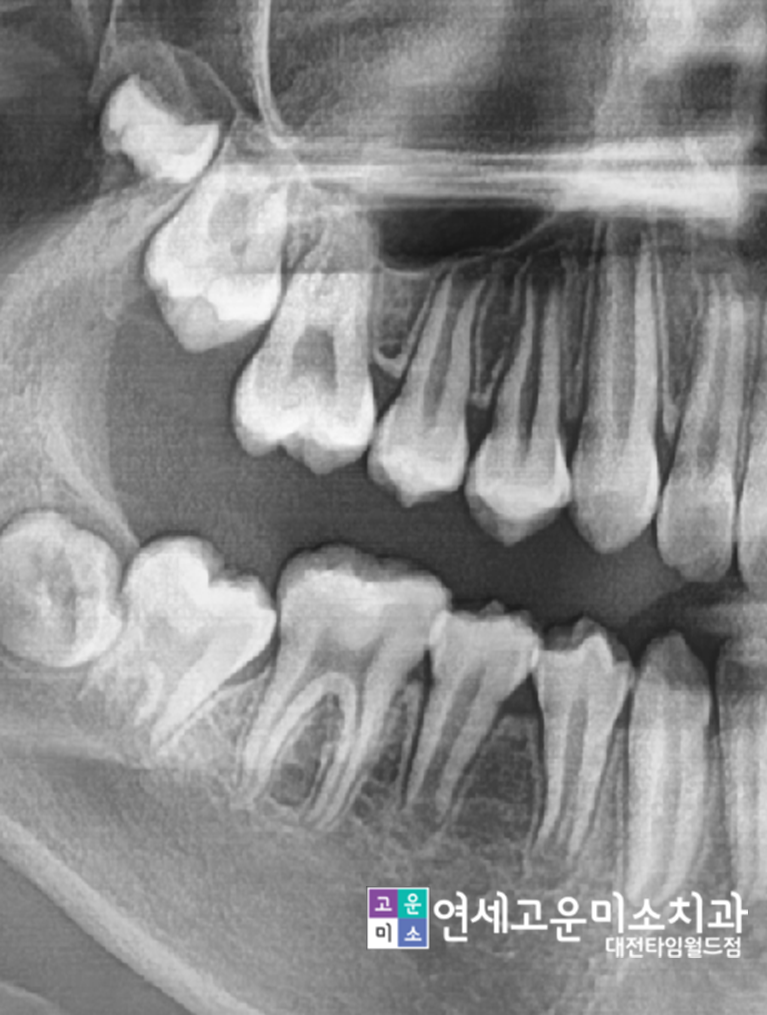

교정이 마무리되었고

큰 어금니도 다시 뒤로 보내어 제자리로 맹출 되게 해주었고

작은 어금니도 잘 맹출 된 것을

확인할 수 있습니다.

Case 3-1. 영구치 맹출 장애

"영구치가 안 나와요"

이번 케이스도 영구치 맹출 장애 케이스지만

훨씬 심각한 경우입니다.

동그라미 친 곳을 보면 영구치가 나올 공간이

전혀 없습니다.

다른 영구치가 나올 때까지 기다렸다 치료하면

그 사이 공간은 점점 더 없어지게 됩니다.

엑스레이를 보시면

영구치가 나올 공간이 얼마나 많이 부족한지

알 수가 있습니다.